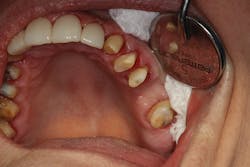

In the first case, a tooth with a subgingival margin preparation has been cleaned with an ultrasonic scaler and is gently dried in preparation for cementation. Note how the margin goes deeper subgingivally on the distolingual (figure 1). With TheraCem, a clean, prepped dentin or enamel surface is all that is needed to achieve excellent bond strengths, with the added benefit of sustained calcium and fluoride release. While TheraCem forms a strong bond to most substrates, including zirconia, a zirconia primer is still used prior to try-in to achieve optimal bond strength and prevent salivary contamination of the zirconia surface (figure 2).

Figure 1: Cleaned and prepared tooth